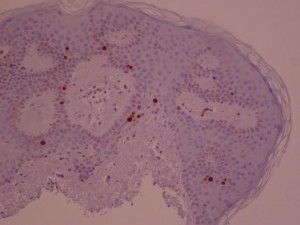

Ki-67 staining of an acantho-hyperkeratotic type of SK. On the last picture, most of the basal staining comes from the accumulation of pigment as the clinical image suggests.

Ki-67 staining of an acantho-hyperkeratotic type of SK. On the last picture, most of the basal staining comes from the accumulation of pigment as the clinical image suggests.

Ki-67 staining of an acantho-hyperkeratotic type of SK. On the last histological picture, most of the basal staining comes from the accumulation of pigment as the clinical image suggests.